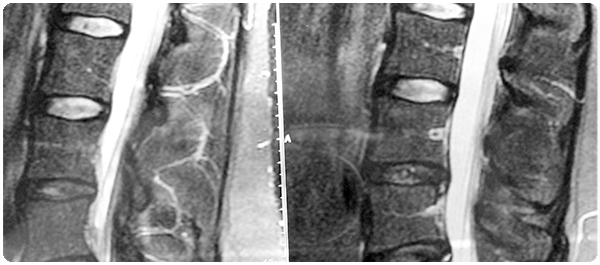

- มีอาการเจ็บบริเวณต้นขา (Thigh) หรือบริเวณขาหนีบ (Groin) เพราะการใช้ยาบิสฟอสโฟเนทเป็นระยะเวลานานอาจเพิ่มความเสี่ยงในการหักของกระดูกต้นขา